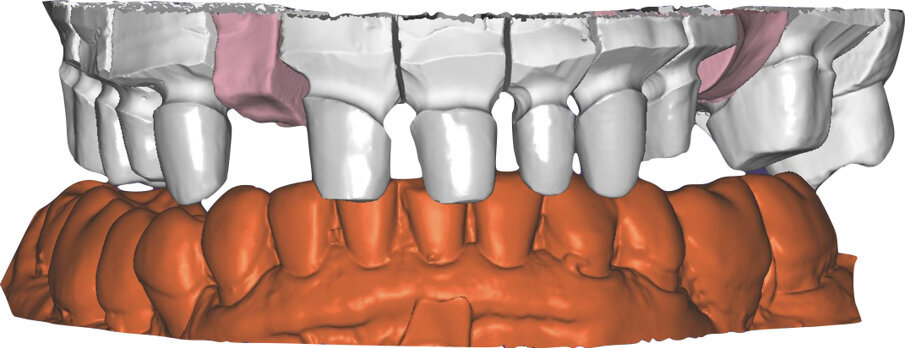

Ciò consente un miglioramento dei rapporti interarcata, un guadagno di spazio protesico in regioni premolari e molari, ed il mantenimento di uno spazio protesico conforme ad una corretta anatomia per i denti vitali da 1.3 a 2.3. Al paziente viene pertanto aggiornato il piano di trattamento e proposta la riabilitazione in TRP, con la previsione di overlays all’arcata inferiore per costruzione del nuovo piano occlusale. In posizione terapeutica sono modellati i coni delle centriche attive sui monconi sfilabili all’arcata inferiore, per la successiva individuazione al CAD con modulo articolatore del piano occlusale studiato. Questo rapporto articolare in TRP è ora scansito con scanner da laboratorio Xanos Evo Scan Compact (Fig. 24).

I modelli sono così importati in corretta posizione spaziale tramite il modulo exocad Virtual Articulator (Fig. 25). Non avendo a disposizione nel CAD l’analogo virtuale dell’articolatore Reference SL, viene impostato il sistema virtuale SAM, che usa lo stesso piano di riferimento axio-orbitale e geometria sovrapponibile al Reference SL. Per la programmazione virtuale dei parametri funzionali dell’articolatore si riesegue l’output dall’axiografia elettronica con Gamma Dental per SAM (Fig. 26). Si procede perciò ora con la modellazione CAD della ceratura mantenendo il riferimento dato dal piano occlusale individuato dai coni di centrica scansiti con l’articolatore (Fig. 27). L’articolatore virtuale consente una prima verifica dei rapporti occlusali tra gli elementi e un abbozzo di funzionalizzazione delle cuspidi con strumenti virtuali dinamici, che permette di arrivare ad un CAD design vicino alla morfologia ricercata (Figg. 28-33). Il modellato è ora fresato in cera Yeti Dental al CAM con fresatore VHF Cam5-S1 ed i denti in cera, tutti singolarmente sfilabili, sono posizionati sui modelli eseguiti con stampa 3D.

Il fresato ottenuto è poi riportato su articolatore Reference SL – già opportunamente programmato – e viene dall’Odontotecnico competente più precisamente funzionalizzato secondo i criteri della programmazione funzionale sequenziale, evidenziando con cere colorate i rapporti di centrica, le funzioni di mediotrusiva e protrusiva e le protezioni retrusive. I monconi sfilabili consentono la modellazione della sequenzialità mediotrusiva con la guida incisale indicata dalla registrazione axiografica (blu) (Figg. 34-37). La ceratura sequenziale è ora scansita con Sirona InEos X5 su Exocad, ed il modellato viene ricontrollato al CAD per spessori, connessioni e morfologia, e nella regolazione degli offsets per la ripreparazione dei monconi, ed è inviato al CAM per la fresatura dei II provvisori in Bredent breCAM.multicom, un PMMA con microriempitivo ceramico ad alta stabilità, su Dental Plus 5 Axis Milling Machine. La rifinitura dei monconi è seguita da ribasatura dei II provvisori in TRP - previo isolamento di tutte le superfici funzionali - e gli stessi sono poi rifiniti e lucidati. I soli elementi 3.3, 4.2 e 4.3 sono rimodellati in regione incisale con addictions in composito, secondo la morfologia studiata in ceratura. La consegna conferma la buona integrazione dei manufatti dal punto di vista estetico, occlusale, articolare e neuromuscolare, con controllo occlusale conforme al progetto (Figg. 38-42).